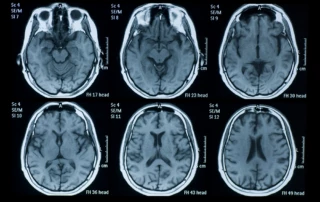

Women, Menopause, and Alzheimer’s Risk

Almost two-thirds of Americans living with Alzheimer’s disease are women. And women in their sixties are more than twice as likely to develop Alzheimer’s disease over the rest of their lives as they are to develop breast cancer.